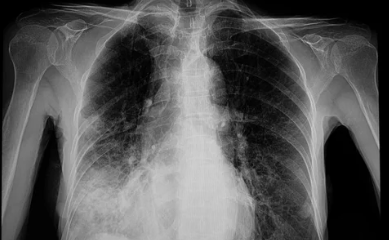

방사선 폐렴은 암 치료 과정에서 발생할 수 있는 부작용으로, 특히 흉부 방사선 치료를 받은 환자에게 나타날 가능성이 높습니다. 초기에는 경미한 증상으로 시작되지만, 적절히 관리하지 않으면 심각한 폐 손상을 초래할 수 있습니다. 이번 글에서는 방사선 폐렴의 대표적인 증상과 이를 조기에 인지하여 관리하는 방법을 소제목별로 자세히 살펴보겠습니다.

방사선 폐렴이 치료 없이 방치되면 폐 기능이 점점 악화될 가능성이 높습니다.

- 폐활량 감소:

폐가 딱딱해지는 섬유화 현상이 진행되면서 숨을 깊이 들이쉬기가 어려워지고, 폐활량이 감소합니다. - 산소 부족 증상:

피부가 푸르스름해지는 청색증이 나타나거나, 운동 중 어지러움이나 혼란 상태가 발생할 수 있습니다. - 만성 폐질환으로 진행 가능성:

초기 단계에서 치료하지 않으면 만성 폐섬유증으로 발전해 장기적인 호흡 문제가 생길 수 있습니다.